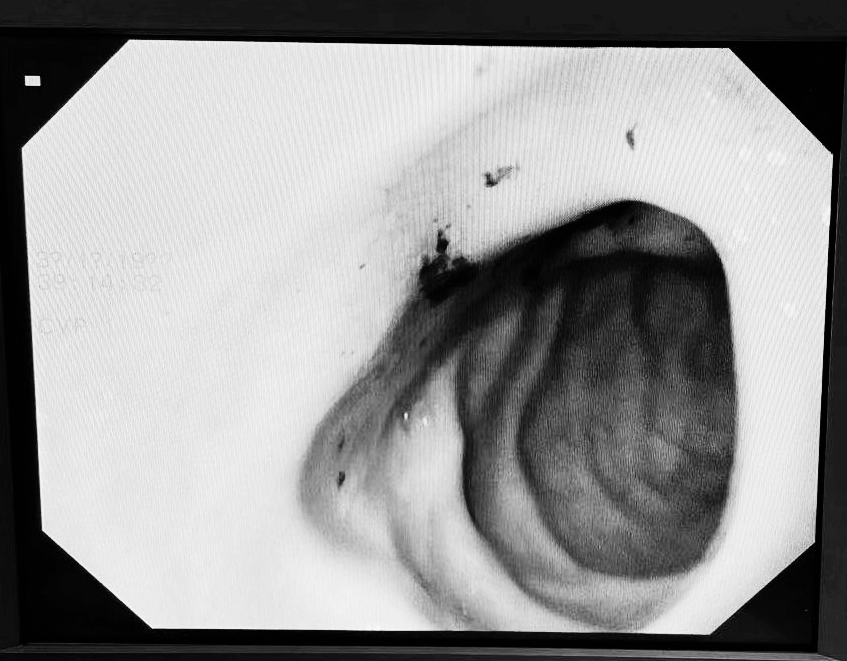

急诊胃镜检查证实,有一块3cm大小的石头嵌顿在了十二指肠球部导致肠腔堵塞。由于老人存在严重心肺功能不全,不能耐受麻醉和腹部手术,我们决定进行胃镜下碎石治疗。在泌尿外科医生的帮助下,我们应用钬激光成功将结石爆破为多个小的碎块,应用网篮将大的碎块经口取出。

胃镜证实胆囊结石阻塞十二指肠